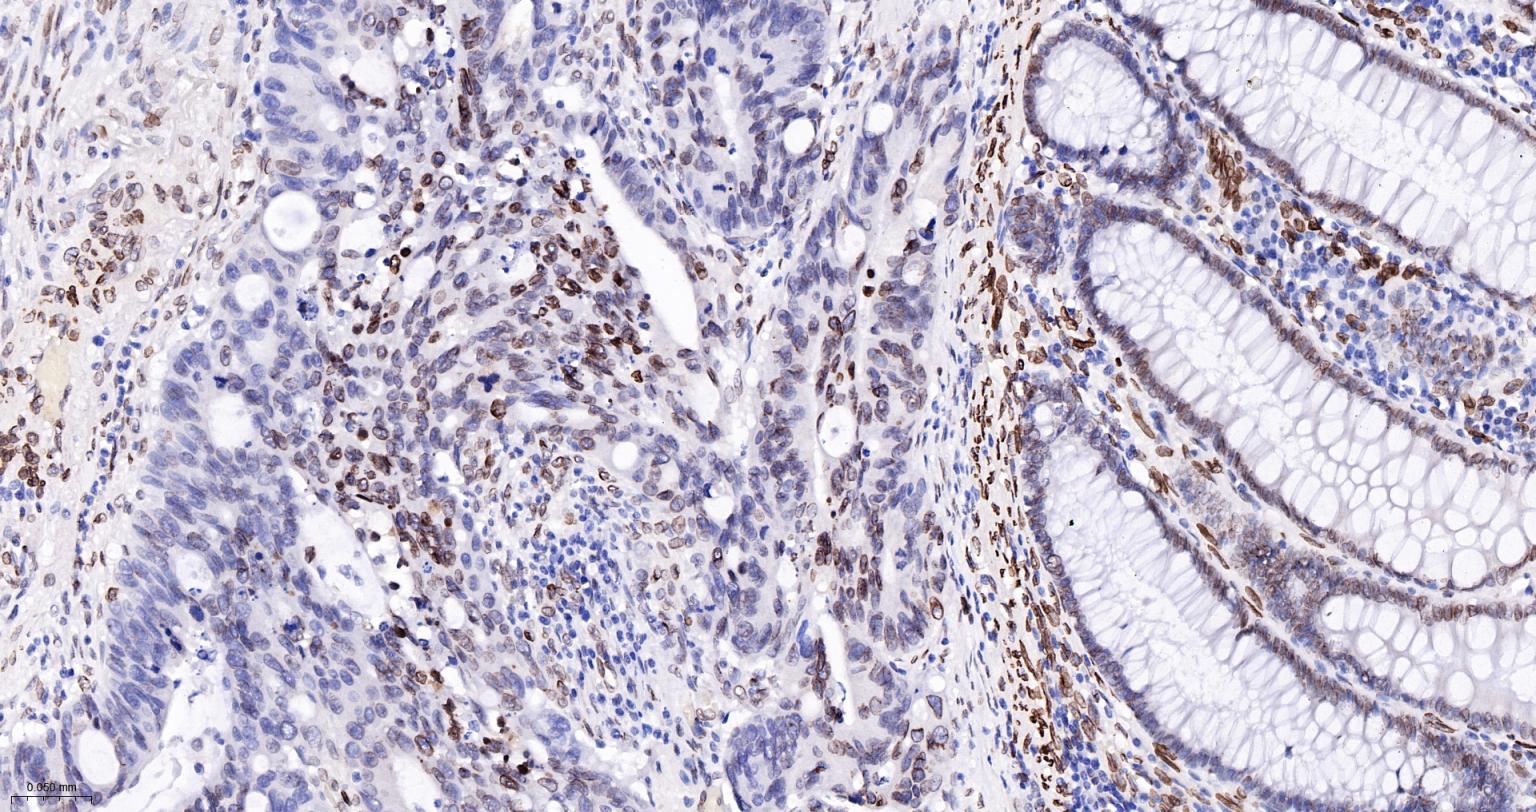

Paraformaldehyde-fixed, paraffin embedded Human Colon Cancer; Antigen retrieval by boiling in sodium citrate buffer (pH6.0) for 15 min; The section was incubated with Lamin A/C Monoclonal Antibody, Unconjugated (bsm-51683M) at 1:100 overnight at 4°C, followed by conjugation to the bs-40296G-HRP and DAB (C-0010) staining.